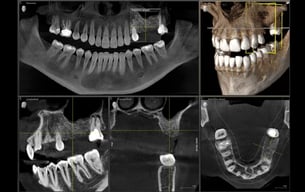

Radiologia, TAC ed Imaging 3D

Analisi dettagliate per trattamenti odontoiatrici precisi.